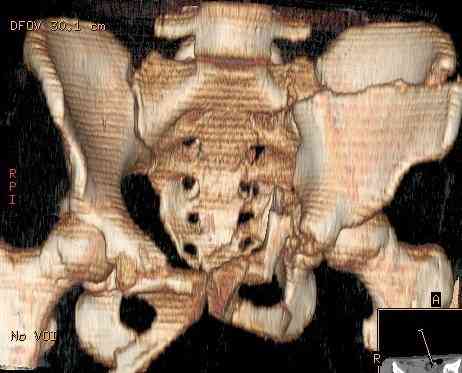

В заключении будет демонстрация операции больной 27 лет с давностью травмы более 2,5 мес.(3D прилагается) Убедительная просьба до 24.11.2008 всем желающим сообщить по адресу: pelvistrauma@mail.ru следующие данные: 1. Ф.И.О. 2. Должность и место работы 3. Контактный телефон. Семинар состоится на базе ГКБ №15 по адресу: г.Москва, ул. Вешняковская, д.23. административный корпус, IV этаж, 1 травматологическое отделение

Остеосинтез подвздошной кости

Укладка тазовой пластины "matta"

Операционная. Оперирует д.м.н. проф. Казанцев А.Б.